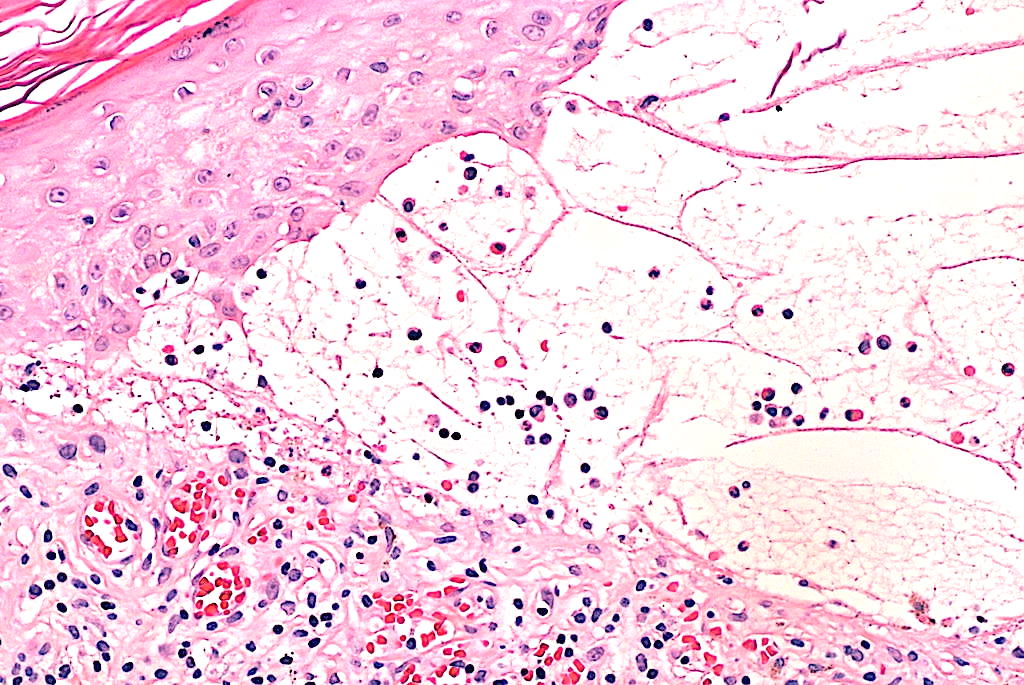

- 1 punch lesional (bula íntegra) para H&E.

- Integrar: clínica compatible + bula subepidérmica eosinofílica + DIF lineal IgG/C3 en membrana basal ± autoanticuerpos BP180/BP230.